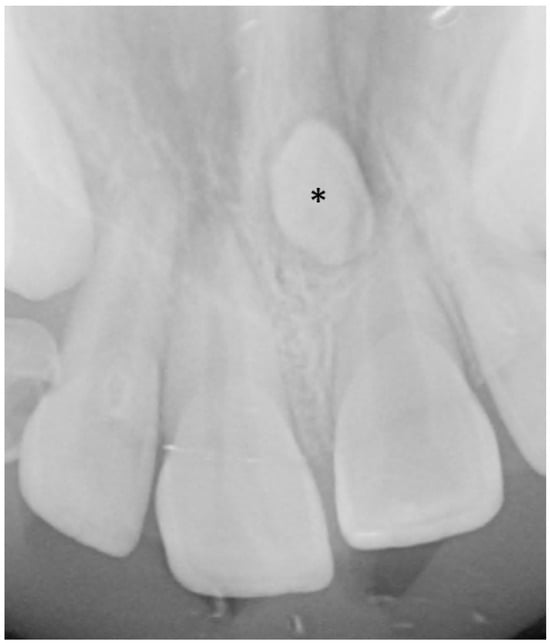

3.5.2. Dental Decay Radiologic Correlations

3.3. Radiologic Correlations of Embryological Development